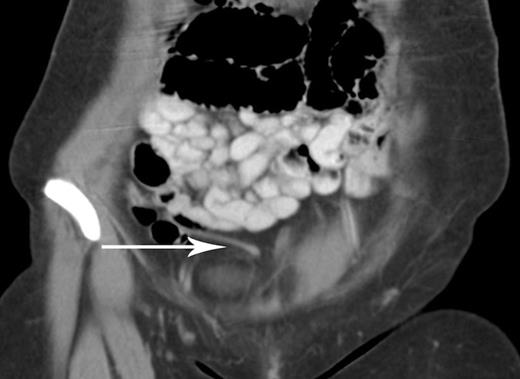

We report a case of a 27-year-old female with abdominal pain accompanied by nausea, vomiting, and anorexia for 24-hours. The patient denied every having experienced similar episodes and she denied any gynecological or urological symptoms. Past medical and surgical history was significant for a total abdominal hysterectomy with right-sided oophorectomy through a low transverse Pfannenstiel incision for stage III cervical cancer. On physical exam the patient had a soft abdomen with focal peritonitis in the right lower quadrant. The Pfannenstiel incision was well healed and intact with no evidence of hernias or masses on palpation. Computed tomography (CT) was performed showing an elongated 5mm appendix (Figure 1). Based on clinical examination we elected to perform a diagnostic laparoscopy suspecting acute appendicitis.